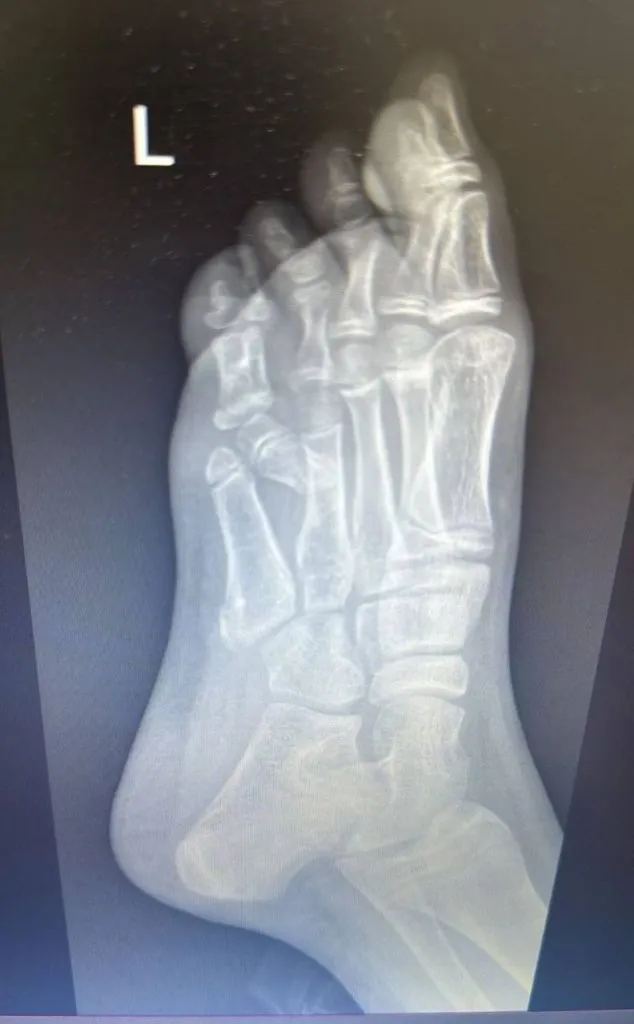

Уникальную операцию провели врачи Алматы для 10-летней девочки-подростка, которая появилась на свет с врожденным дефектом — шестым пальцем на левой ноге, передаёт CMN.KZ

«Сложность операции заключалась в том, что перед нами стояла задача не просто удалить дополнительный палец, а ещё и плюсневую кость, которая давала ненужную аномальную ширину стопе. Также при обследовании выявили аномалию расположения нервов и кровеносных сосудов, что требовало работы под микроскопом», — рассказал заведующий отделением травматологии ДГКБ № 2 Ерлан Садырбалин.